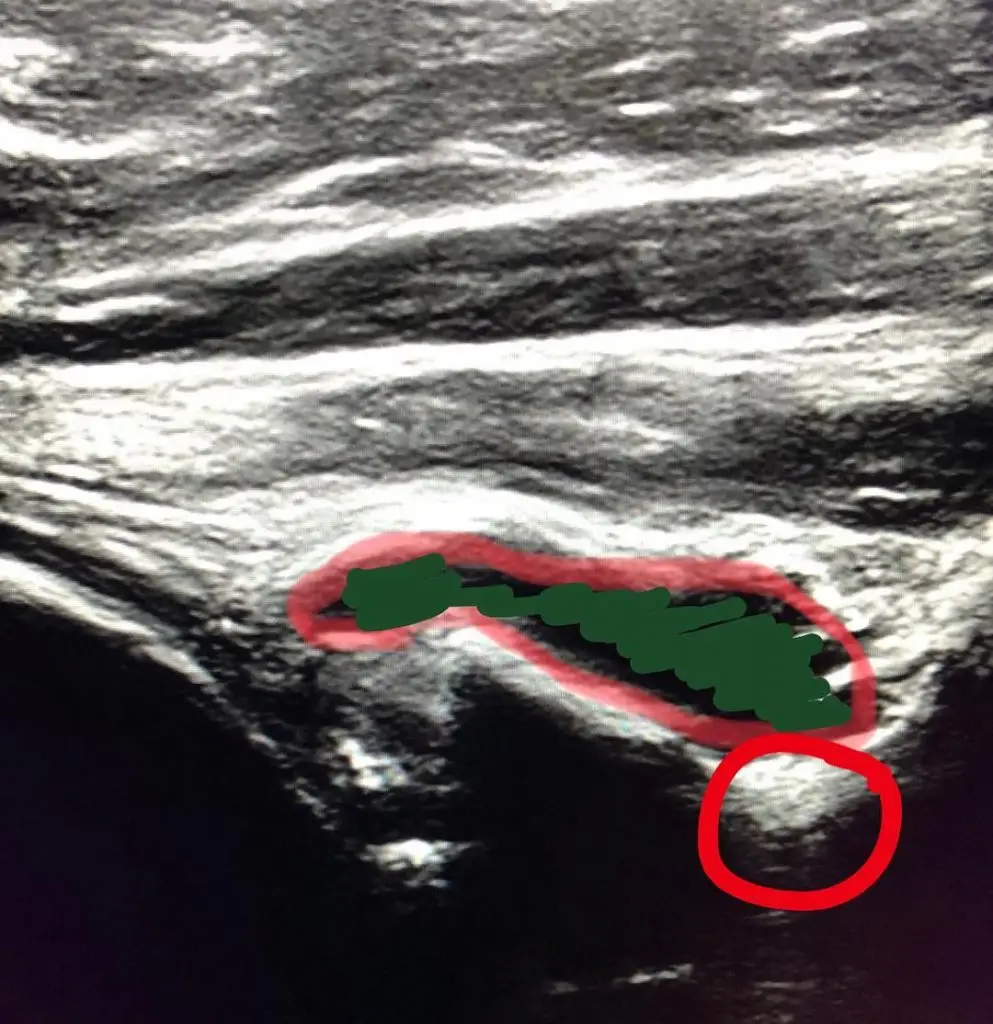

I realize this post may not be super popular but if you love anatomy, read on… About two weeks ago I had a sudden onset of left shoulder external rotation weakness. I immediately started to pull together some plausible differential diagnosis and came up with a possible infraspinatus tear or something neurological. I didn’t have […]